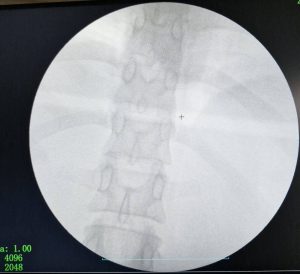

كان المستشفى الرئيسي قد استقبل فتاة تبلغ من العمر ٣٠ عاما، تعاني من آلام حادة ومزمنة بالبطن، ومن خلال تقصي التاريخ المرضي، تبين أنها ابتلعت إبرة خياطة عن طريق الخطأ منذ ما يقرب من ٤٠ يوماً، وعلى الفور، تم إجراء الفحوصات اللازمة والأشعة المقطعية التي أظهرت أن الإبرة لم تكتفِ باختراق جدار المعدة، بل استقرت في موقع تشريحي دقيق جداً بجوار الشريان الكبدي والوريد البابي الكبدي.

وقام الفريق الطبي الذي ضم كل من، الدكتور محمود حسب النبي، أستاذ مساعد بقسم الجراحة، والطبيب حماده فتحي، والطبيب خالد حسان، والطبيب حسام محمود، مدرسين مساعدين بالقسم، والطبيب ماريو أيوب طبيب مقيم بالقسم، ومن قسم الأشعة التشخيصية والتدخلية، فريق طبي تحت إشراف الدكتور حسن مجلي، رئيس القسم، وضم كل من الدكتور حمدي إبراهيم، أستاذ مساعد بقسم الأشعة التشخيصية، والطبيب ميرنا يوسف، مدرس مساعد بالقسم، يعاونهم فريق طبي من قسم التخدير جاء تحت إشراف الدكتورة هالة سعد، رئيس القسم، وضم كل من الدكتور جورج مجدي، مدرس بالقسم، والطبيب أمونيوس خليل، مدرس مساعد بالقسم، كما عاونهم أماني أحمد، تمريض بقسم الجراحة، وحسن علي، فني الأشعة، باستخدام جهاز الأشعة C-Arm، بدلاً من اللجوء إلى الجراحة التقليدية (فتح البطن الاستكشافي)، التي تتطلب وقتاً أطول للتعافي، لرصد مكان الإبرة بدقة متناهية.

ونجح الفريق الطبي في استخراج الإبرة بالكامل باستخدام المنظار الجراحي عبر (٣) فتحات صغيرة فقط في جدار البطن.